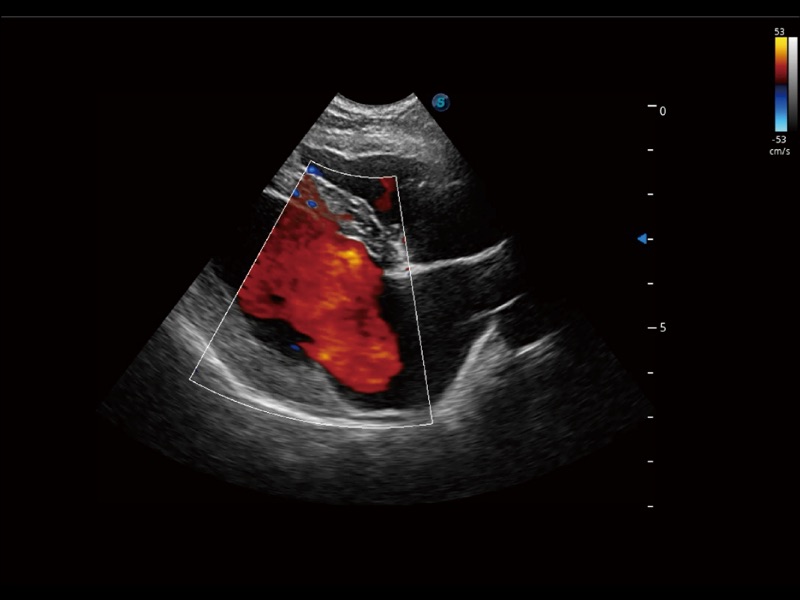

通過(guò)創(chuàng)新的 Matrix E自適應(yīng)濾波器和超長(zhǎng)時(shí)間域算法,極大提升超低速微細(xì)血流的檢出能力,同時(shí)更精準(zhǔn)地濾除軟組織和噪聲信號(hào),為獸用醫(yī)生提供以往無(wú)法通過(guò)常規(guī)血流獲得的疾病診斷信息。

通過(guò)色彩血流和實(shí)時(shí)寬景相結(jié)合,可觀察到完整的靜脈或動(dòng)脈的血流,方便醫(yī)生檢查。實(shí)時(shí)掃查過(guò)程中,如有任何操作失誤也可以很容易地進(jìn)行回掃擦除,而不會(huì)中斷掃查。